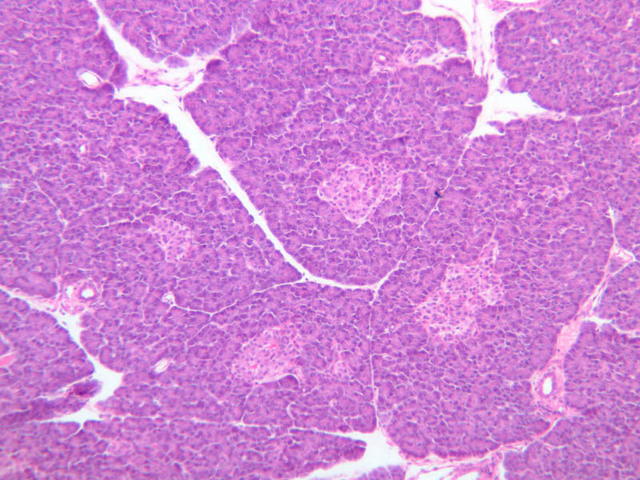

Scan slide B-36 (H&E [10x, 20x] [10x, 20x). Note that in this H&E preparation most of the pancreas consists of rather compactly arranged, darkly stained cells. The compact, darkly stained regions constitute the exocrine portion of the pancreas. (Of what organ does the exocrine pancreas remind you?) The endocrine portions of the pancreas consist of small bits, or islands, of more lightly stained tissue that is somewhat irregularly dispersed within the substance of the exocrine pancreas. Drawing on the name of their discoverer, the endocrine portions of the pancreas are known as the islets of Langerhans.

Using the high dry objective (B-36, H&E [40x, 40x-labeled]), study the structure of several acini. Note that the acinar cells are pyramidal in shape; note also that the acinar cells are clearly polarized: their basal cytoplasm (periphery of acinus) is quite basophilic, owing to large accumulations of RER, whereas their apical cytoplasm contains many acidophilic granules (zymogen granules) (B-36, H&E [10x, 20x, 40x-labeled]).

Now turn your attention to the system of pancreatic ducts. As you look for duct elements, bear in mind that the nuclei of duct cells tend to stain more lightly and to have less prominent nucleoli than do those of acinar cells. Begin by studying a number of different acini until you have identified several examples of centroacinar cells, which represent the initial segment of the duct system. Centroacinar cells are usually evident as lightly stained nuclei that lie, individually or in clusters of two or three, near the center of an acinus. Now look along the boundaries between acini for intercalated ducts (B-36, H&E [10x, 20x, 40x-labeled] [10x, 20x, 40x]), which appear in longitudinal section as trains of elongate, lightly stained nuclei and in transverse section as closely spaced, lightly stained nuclei surrounding a small lumen. Intercalated ducts drain into intralobular ducts, which are distinguished by their larger diameter. It is best to use the 10X objective as you begin your search for intralobular ducts (B-36, H&E [10x, 20x, 40x-labeled] [10x, 20x, 40x]). You want to be on the lookout for arrays of closely spaced nuclei surrounding a lumen. Conclude your study of the duct system by examining the connective tissue between pancreatic lobules for interlobular ducts, which may vary in caliber and epithelial lining (B-36, H&E [10x-labeled, 20x, 40x]).

Endocrine pancreas

Although H & E staining permits ready identification of the islets of Langerhans, it does not permit differentiation of the various cell types that comprise the islets (B-36, H&E [10x, 20x, 40x-labeled]). There are no slides in the class collection that permit identification of all of the cell types of the endocrine pancreas. However, the sections on slides B-37 and B-40 permit specific identification of two cell types. Slide B-37 has been stained by the aldehyde fuchsin technique, which lends a magenta coloration to the granules of the insulin-producing B-cells. All other cells in the islets stain a dirty orange color (B-37 [10x, 20x, 40x] [10x, 20x, 40x]). Most of these orange-colored cells are the glucagon-secreting A-cells; however, you should bear in mind that somatostatin-secreting D-cells, as well as APUD cells that secrete pancreatic polypeptide are also scattered about the islet. The section on slide B-40 has been prepared by a silver impregnation method that renders some of the APUD cells in the islets (which appear as “clear cells” in ordinary preparations) dark brown or black (B-40 [10x, 20x, 40x]).